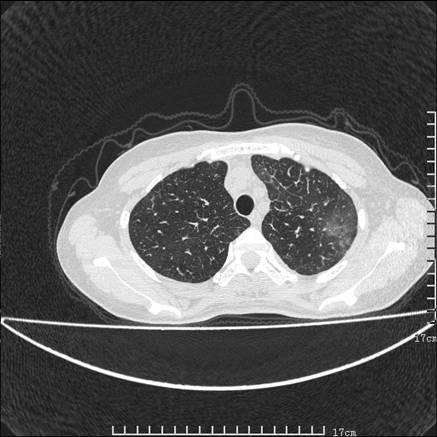

女,46岁,患胃溃疡多年,溃疡大小约1.0cm左右,后于5年前手术,病理为胃癌。主诉:半月前感冒后胸闷,气短,有咳嗽,无明显咳痰,无发热。偶有腰背部不适。

以下为高分辨扫描图像

肺癌性淋巴管炎征象分为主要征象及合并征象,主要征象包括:

1、近肺门支气管血管周围间质结节状增厚;

2、小叶间隔结节状增厚;

3、小叶中央间质结节状增厚;

4、胸膜下间质结节状增厚。

合并征象为:纵隔淋巴结增大,胸腔积液,肺多发随机分布的小结节等。